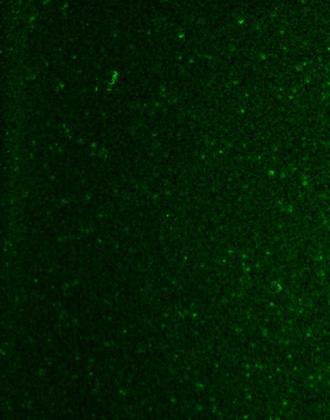

Microfoto van de nimfenvorm (spirocheten) van de Borrelia-bacterie.*

Micronutriënten-synergiën zijn even effectief als het antibioticum Doxycycline, in het remmen van de groei van de Borrelia-spirocheet.

In de eerste reeks experimenten hebben we een combinatie van geselecteerde microvoedingsstoffen onderzocht, ten opzichte van het meest gebruikte antibioticum (Doxycycline), op hun effectiviteit bij het doden van Borrelia-spirocheten. De bovenstaande grafiek toont aan dat de micronutriënten net zo effectief waren als het antibioticum.